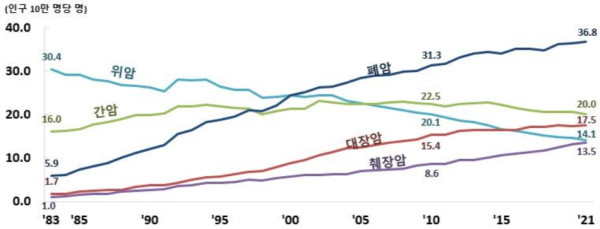

1983년부터 2021년까지의 암 종별 사망률 추이를 살펴보면 급격하게 상승한 폐암 사망률을 확인할 수 있다.

인구 10만명당 폐암 사망률은 1983년 5.9명이던 것이 2021년에는 36.8명으로 급증하는 등 2021년 통계에서 남녀 모두 국내 암 사망률 1위를 차지하고 있다.

2위에 오른 간암으로 인한 사망률(2021년 20.0명)보다 2배 가까운 수치이다.